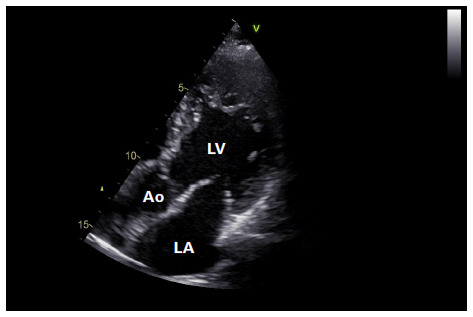

Abstract Image